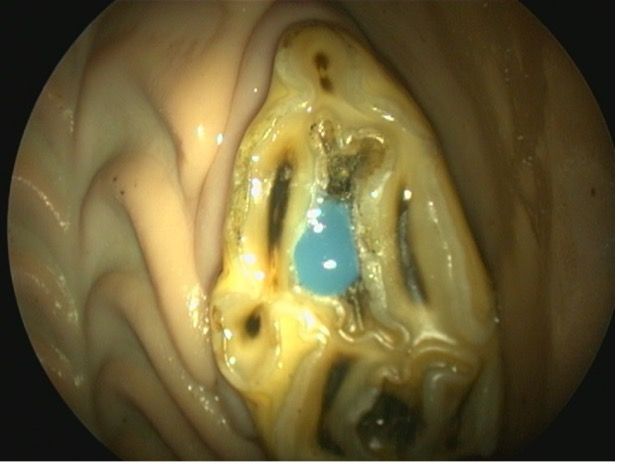

This condition primarily affects the intra-alveolar aspect of the teeth, most commonly incisors and canines, although cheek teeth can also be affected. Odontoclastic cells have been found to cause resorptive lesions extending into the cementum, enamel, dentin, and even the pulp, causing a marked loss of normal architecture in some teeth.13,14 This painful condition can present with absent to variable clinical signs, including masticatory problems. The veterinarian often makes the diagnosis by oral examination and radiographs (Figure 4) or advanced imaging. Findings upon oral examination include gingivitis, fistula formation, gingival recession, deposition of calculus, and swelling or abnormal tooth mobility. Tooth resorption and bulbous enlargement are frequent features on radiographic examination. Currently, surgical extraction of the affected teeth is the treatment option of choice. Supportive therapy with systemic antibiotics, anti-inflammatories, and local mouthwash has been shown to provide only short-term relief of symptoms at best.15